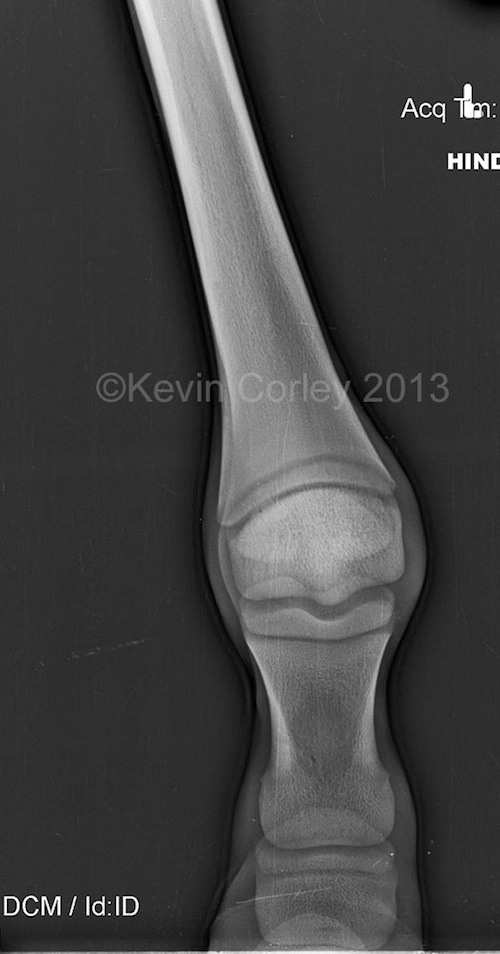

Fran Jurga`s Hoofcare + Lameness On the Case Combined Contracture and

From hoofcare.blogspot.com